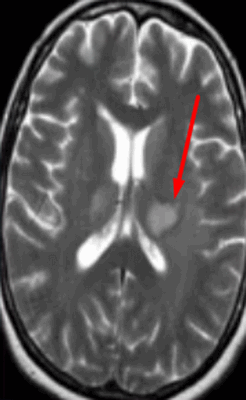

- Стадия 1 (острая): До 4 нед. после повреждения на традиционных МР-изображениях не определяются патологические изменения сигнала.

- Стадия 2 (подострая): Спустя 4-14 нед. на Т2-ВИ визуализируется гипоинтенсивная зона, обусловленная начальным, а не биохимическим распадом миелина и компонентов аксона.

- Стадия 3 (хроническая): Гиперинтенсивная зона на Т2-ВИ (распад жиров и липопротеинов, вазогенный отек, глиоз).

- Стадия 4: Атрофия

- Раннее выявление возможно при использовании метода переноса намагниченности (ПМ) и диффузионно-взвешенных изображений.

Валлеровская дегенерация вследствие инсульта в бассейне средней мозговой артерии в левом полушарии большого мозга. Р1_А1К-изображения (а, b) и Т2-ВИ в аксиальной плоскости (с). В зоне, кровоснабжаемой левой средней мозговой артерией, визуализируется кистозный дефект с глиозом (а). Определяется повышенная интенсивность сигнала от пирамидного пути в левой ножке мозга (b) и в продолговатом мозге слева (с).